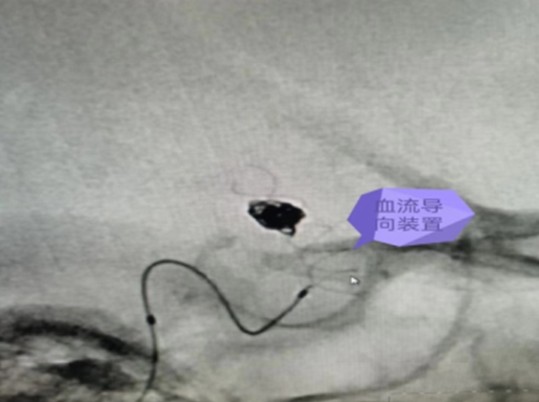

我院成功完成一例顱內(nèi)血泡樣動脈瘤血流導(dǎo)向裝置植入彈簧圈栓塞手術(shù)

通訊員周利軍報:近日,衡陽市中心醫(yī)院神經(jīng)外科團隊成功完成一例顱內(nèi)血泡樣動脈瘤血流導(dǎo)向裝置植入+彈簧圈栓塞手術(shù),術(shù)后患者恢復(fù)良好,術(shù)后10天復(fù)查腦血管造影提示動脈瘤未見未顯影,患者住院16天康復(fù)出院。該手術(shù)標(biāo)志該院神經(jīng)外科團隊顱內(nèi)動脈瘤的介入治療技術(shù)邁入一個新的高度。

衡陽市中心醫(yī)院神經(jīng)外科主任李遠志緊急組織醫(yī)師團隊開展術(shù)前討論,分析認(rèn)為結(jié)合該動脈瘤的形態(tài)及部位等特點,診斷為右側(cè)后交通段血泡樣動脈瘤,再次破裂風(fēng)險極高,建議積極手術(shù)治療。手術(shù)開顱夾閉手術(shù)風(fēng)險高,難度大,而常規(guī)支架輔助+彈簧圈栓塞后期動脈瘤進展及復(fù)發(fā)可能性高。較好的治理方式為血流導(dǎo)向裝置置入+彈簧圈栓塞治療,并取得家屬同意。

7月14日,在麻醉科及介入手術(shù)室的密切配合下,神經(jīng)外科醫(yī)師團隊順利完成了此例后交通段血泡樣動脈瘤血流導(dǎo)向裝置+彈簧圈栓塞手術(shù),拆除了龍女士腦子里的“不定時炸彈”。

據(jù)悉,顱內(nèi)血流裝置(PED)是一種治療顱內(nèi)復(fù)雜動脈瘤新型的治療方式,通過置入所到病變動脈后,使動脈內(nèi)的血流動力學(xué)發(fā)生改變,緩慢的在動脈瘤內(nèi)形成血栓,內(nèi)膜上皮攀爬到支架表面從而來修復(fù)病變血管使其發(fā)生血管重建來修復(fù)病變的載瘤動脈。血流導(dǎo)向裝置的發(fā)展更新了動脈瘤的治療理念,對顱內(nèi)復(fù)雜動脈瘤的治療結(jié)果產(chǎn)生革命性的變化,具有手術(shù)微創(chuàng),操作簡單,安全性相對較高,在降低動脈瘤復(fù)發(fā)方面更具有優(yōu)勢。